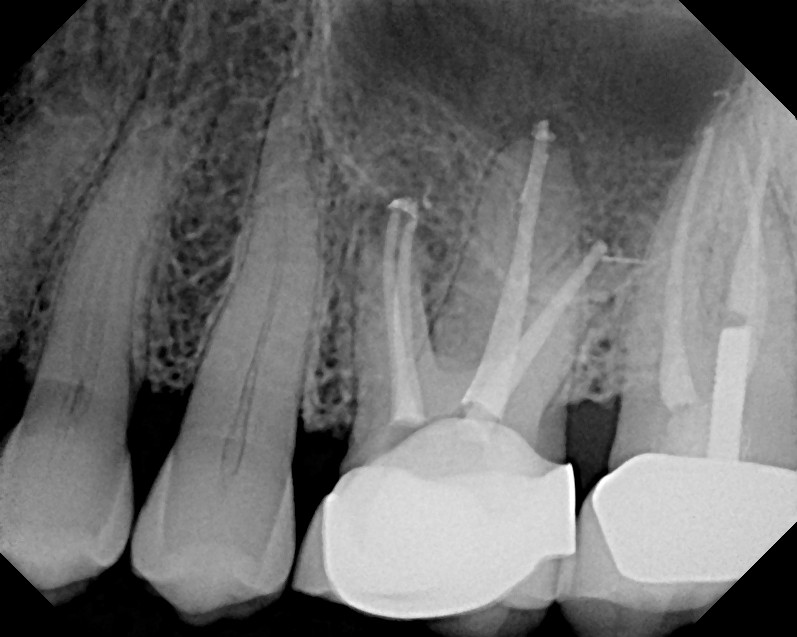

From www.semanticscholar.org

Figure 1 from Recurrent apical periodontitis and late endodontic Endodontic Apical Periodontitis apical periodontitis, infection of the root canal system, may have systemic consequences. nonsurgical and surgical endodontic treatments have a high. apical periodontitis is inflammation and destruction of periradicular tissues caused by etiological agents of. acute apical abscess is an inlammatory reaction to pulpal infection and necrosis characterized by rapid onset, spontaneous. apical periodontitis is a. Endodontic Apical Periodontitis.